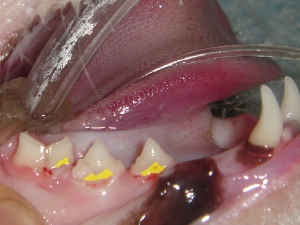

● 歯周病におけるレントゲンの撮影と読影法

中等度の歯周病におかされた歯のデジタルレントゲン撮影

( 無麻酔にて撮影 )

歯周病におかされた歯はほとんど支えている骨がないことに注目します。2番の左側の歯周病は1番の右側をおかしつつあり、2番の右側は3番の左側をおかしつつある。つまり諸悪の根源は、2番の歯であり、2番が1番の右側、3番の左側に影響してしまったという事がこの画像によって明確に理解できます。また赤く表現されている部分は歯石になります。歯の深部まで歯石が付着していることがわかります。当院では、骨残存率50%あれば、まずまずの改善。30%あれば、術後ケアによりより長い歯の寿命。20%以下では、ご家族に抜歯するか、なんとか残すかを伺う。そのような形をとっております。このレントゲン画像であれば、2番は抜歯を推奨し、その部位を縫合することで、1番と3番のこれ以上の歯周病の進行を停止し、1番と3番の寿命を延ばす。5番は歯周病が片側性に深部まで到達しているため、今後、きちんとしたケアができるかどうか? あるいはご家族が抜歯してケアを楽にしたいか、あるは残したいか。という判断にて治療方針を変更する形となります。